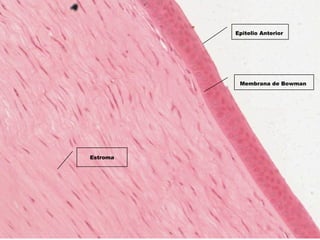

Estroma

Membrana de Bowman

Epitelio Anterior

Membrana de Descement

Endotelio Corneal